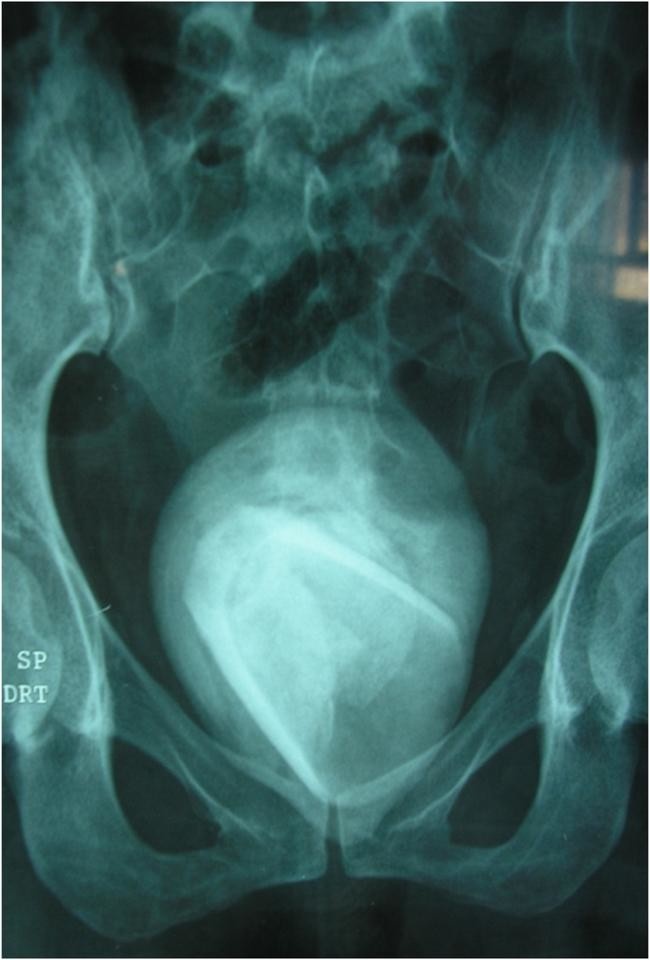

Рентген показал «прямоугольную форму» внутри ее мочевого пузыря, которая напоминала стакан, и большой камень мочевого пузыря вокруг него размером 8 см на 7 см.

Но сканирование показало, что у женщины, личность которой не называется, вырос «гигантский» камень мочевого пузыря шириной 8 см, который полностью покрывал нечто, похожее на стакан для питья. Женщина, чей случай был опубликован в медицинском журнале, призналась, что использовала стакан в качестве секс-игрушки, когда ей было чуть за 40.